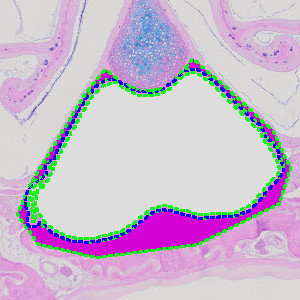

Figure 2

Close-up on nasal cavity with manually outlined region of interest.